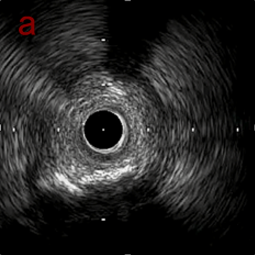

a,b,cはさらに石灰化に食い込み、石灰化量は減少。

それに伴いdではbiasがさらにtentingのIVUS所見にへんかしhigh injury riskと思われた。

引き続き造影で確認してpinpointで引きのOAS high speedを3回さらに追加のためcでIVUSマーキングを行い、その点より引きで赤線のpinpoint OAS high speedを行い、dに関してはinjury回避のためにOASを当てない方針とした。

IVUS after OAS high speed 3回追加

IVUS imaging after high speed 3回追加

a,b,cの十分な石灰化のsanding。

High riskのbias所見へと変わっていったdの部位に関してはpinpoint OASを行うことでinjuryなく治療できた。